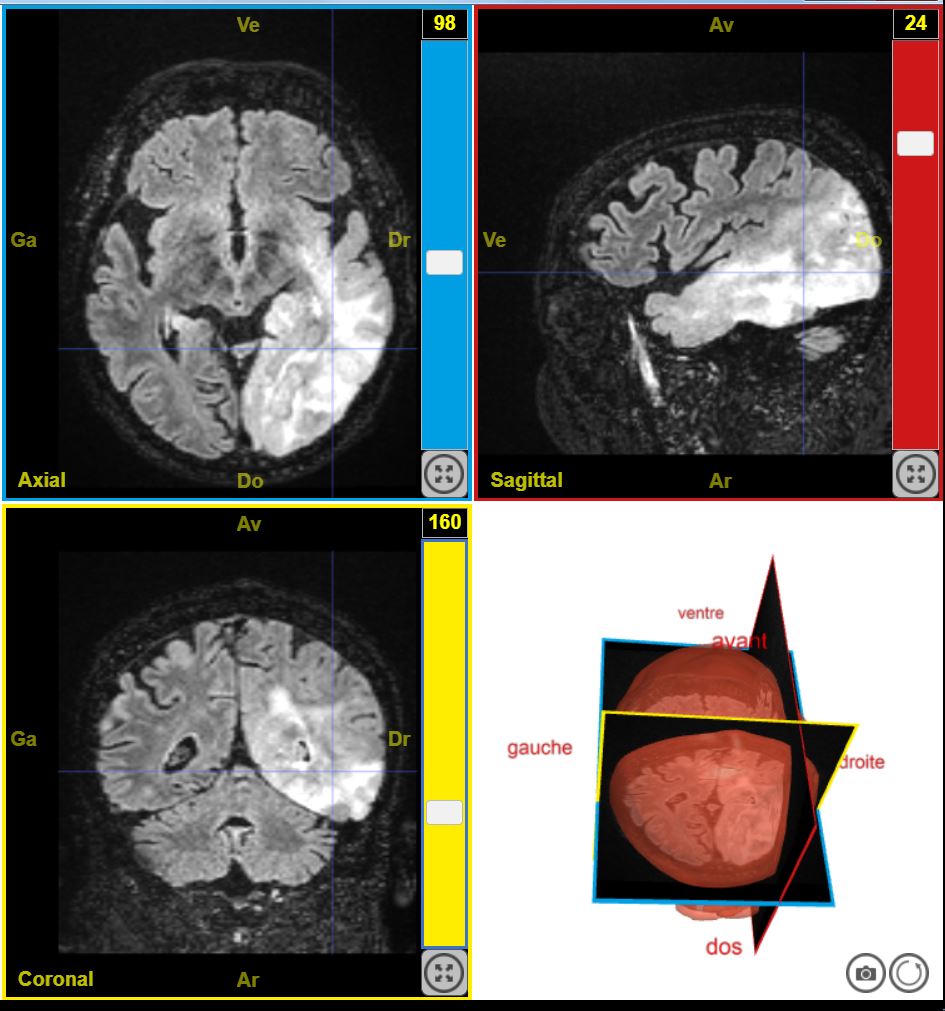

12224PathologieTumeurTroubleSensitifGauche T2Flair

Par Sandrine Beaudin